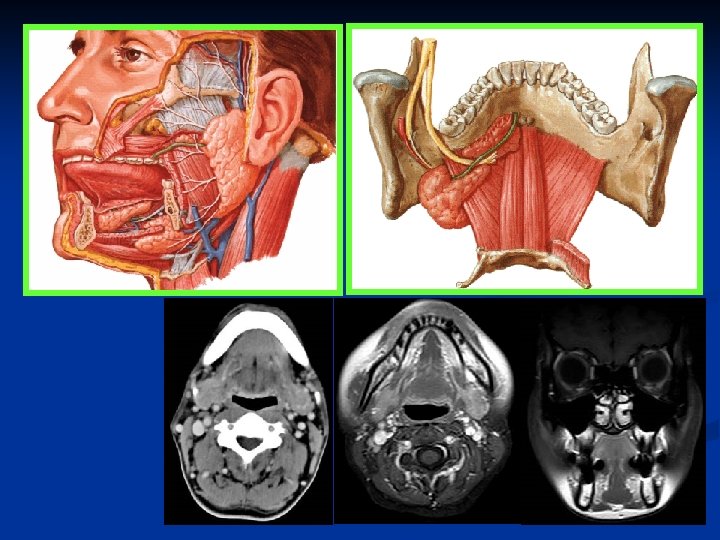

Salivary glands n n Parotid glands Submandibular glands Sublingual glands Minor: tongue, cheeks, lips, palate

Parotid glands The largest of the salivary glands n The duct to this gland (also known as Stensen’s duct) empties within the buccal cavity (the inside of the cheek). n The facial nerve (CNVII) runs through this gland n

Submandibular glands n The Submandibular Gland secretes saliva into ducts called 'Warton's Ducts'. These ducts open on either side of the lingual frenulum.

Sublingual glands n Lie anterior to the submandibular glands under the tongue, beneath the mucous membrane of the floor of the mouth. They are drained by 820 excretory ducts. The largest duct, the sublingual duct (of Bartholin) joins the submandibular duct to drain through the sublingual caruncle.